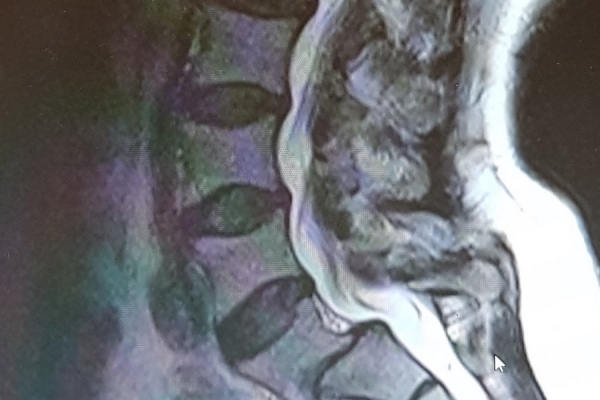

BEL KAYMASINDA CERRAHİ

Bel kayması omurilik basısı olşturduğu zaman cerrahi olarak tedavi edilebilir. Halk arasında platin diye tabir edilen titanyum vidalar ile kayma orijinal yerine oturtulur, ancak en önemlisi vidalara olan baskının azaltılması ve kaynamayı sağlamak için kullanılan eklem mesafesine yerleştirilen protezlerdir. Ayrıca bu ameliyatlar bel kemiğinin ortasındaki kemikler alınmadan, mikrocerrahi yöntem ile yapılırsa, komşu segment hastalığı riski de azaltılır ve omurganın orijinal hali korunmuş olur.